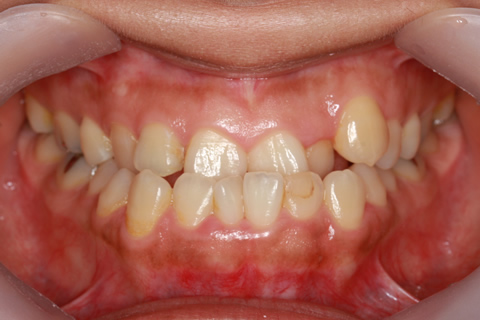

受け口(反対咬合)の症例

症例一覧